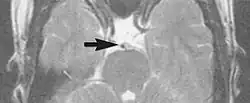

Motion artifacts

A motion artifact is one of the most common artifacts in MR imaging.[2] Motion can cause either ghost images or diffuse image noise in the phase-encoding direction. The reason for mainly affecting data sampling in the phase-encoding direction is the significant difference in the time of acquisition in the frequency- and phase-encoding directions.[1] Frequency-encoding sampling in all the rows of the matrix (128, 256 or 512) takes place during a single echo (milliseconds). Phase-encoded sampling takes several seconds, or even minutes, owing to the collection of all the k-space lines to enable Fourier analysis. Major physiological movements are of millisecond to seconds duration and thus too slow to affect frequency-encoded sampling, but they have a pronounced effect in the phase-encoding direction. Periodic movements such as cardiac movement and blood vessel or CSF pulsation cause ghost images, while non-periodic movement causes diffuse image noise (Fig. 1). Ghost image intensity increases with amplitude of movement and the signal intensity from the moving tissue. Several methods can be used to reduce motion artifacts, including patient immobilisation, cardiac and respiratory gating, signal suppression of the tissue causing the artifact, choosing the shorter dimension of the matrix as the phase-encoding direction, view-ordering or phase-reordering methods and swapping phase and frequency-encoding directions to move the artifact out of the field of interest.[1]